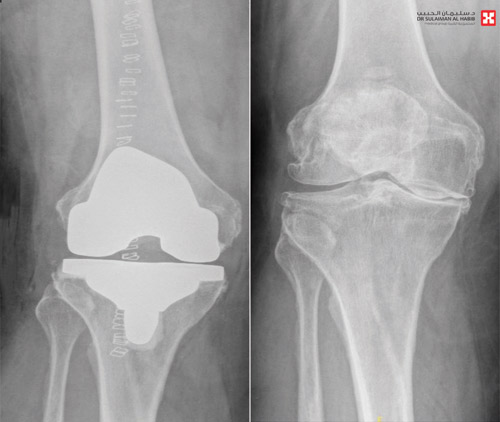

تمكن مستشفى الدكتور سليمان الحبيب بالحمراء من إجراء عملية نوعية وناجحة لاستبدال مفصل الركبة، لـمريض ستيني عانى من الخشونة والاحتكاك الحاد وتلف الغضاريف، وغيرها من التبعات الحادة، ذكر ذلك د. نايف بن نويهض الشهراني استشاري جراحة العظام واستبدال المفاصل رئيس الفريق الطبي المعالج.

وقال د. الشهراني، أن المريض راجع المستشفى وهو يشكو من عدة أعراض كالآلام المتزايدة والتورم وتغير شكل مفصل الركبة، بالإضافة إلى ضعف الحركة وصعوبتها، مع عدم الثبات عند محاولة تحمل الوزن، وأكدت الفحوصات الدقيقة التي أجريت له وجود تآكل في عظمة المفصل، وارتخاء الأربطة الجانبية، وخلل في حركة مفصل الركبة.

وخلص الفريق الطبي إلى أن هنالك إمكانية لإجراء عملية لاستبدال المفصل، وبالفعل أجريت للمريض العملية وتم فيها استبدال مفصل الركبة بمفصل صناعي يناسب الحالة، وتكللت العملية ولله الحمد بالنجاح، وتمكن المريض من المشي بعد العملية مباشرة.

وأوضح د. الشهراني أن الفريق الطبي استخدم تقنية متطورة في إجراء العملية، حيث قام بمحاكاة تشريح الركبة إلى مرحلة ما قبل الخشونة، وهذا يجنب المرضى الصعوبات المتمثلة في الآلام الحادة بعد العملية، وطول مدتي التنويم والعلاج الطبيعي والتأهيل، والتي كانت تجعل المرضى يترددون كثيراً قبل اتخاذ قرار الخضوع لعمليات الاستبدال، على الرغم من أن أعراض الاحتكاك والخشونة تحول حياتهم إلى معاناة دائمة، بسبب الآلام المستمرة، وعدم القدرة على الحركة والنوم وممارسة الحياة بشكل طبيعي. وأشار د. الشهراني أن المستشفى قام بتدريب المريض على كيفية السير على قدميه قبل إجراء العملية.